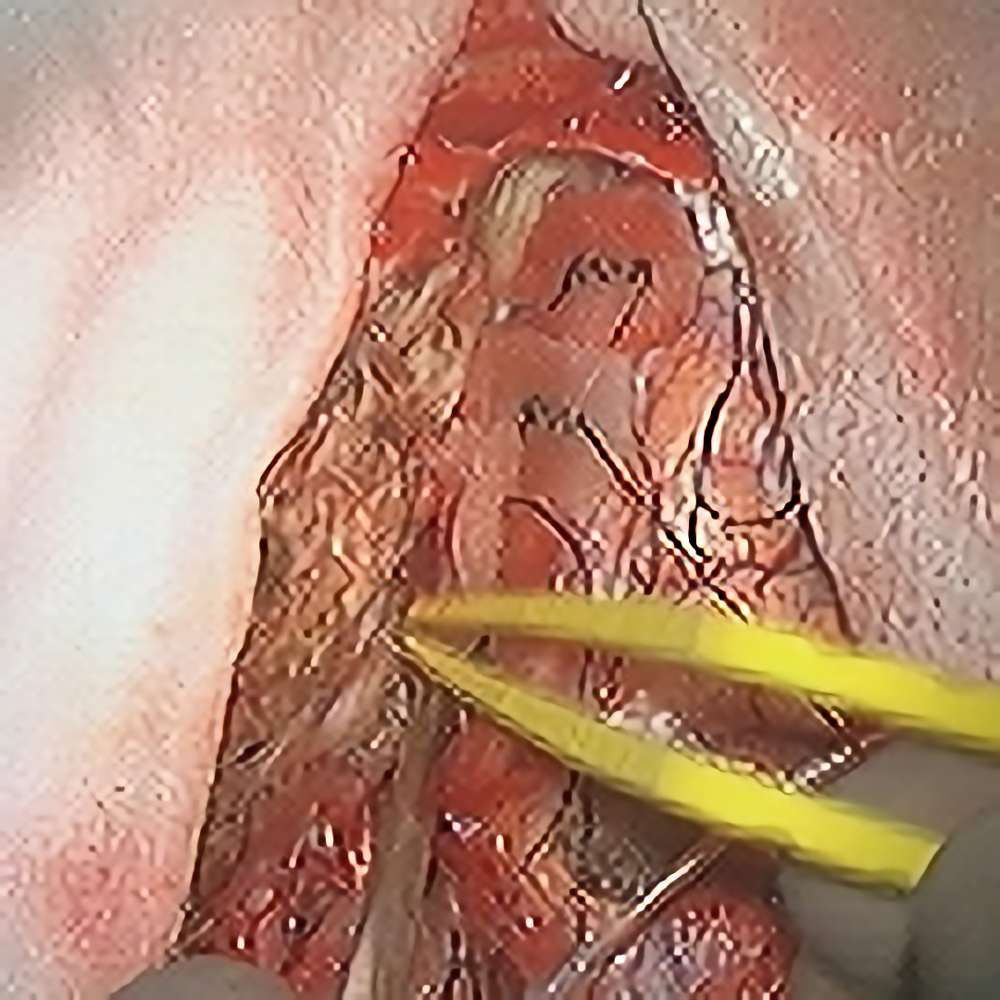

183

'21年6月

50代

小脳血管芽腫

頭蓋内腫瘍摘出術

No.’21_27 手術前1

No.’21_27 手術前2

No.’21_27 摘出 前

No.’21_27  摘出 中

No.’21_27 摘出 後